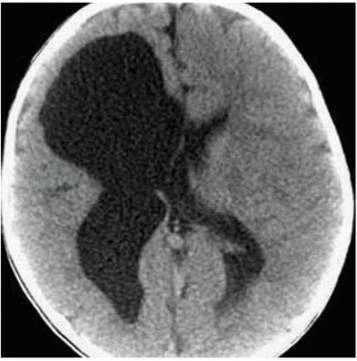

(二)CT

CT扫描主要表现为脑实质内边界清楚的脑脊液性低密度区,并与脑室相通,同侧脑室扩大,可伴有不同程度的脑发育不全和/或局部脑组织萎缩(图1),增强扫描时囊壁无强化。CT扫描不仅能确诊,而且对了解囊肿的大小、部位、形态、数目及治疗方案的选择、预后估计、鉴别诊断等均有重要意义。

图1脑穿通畸形的CT表现